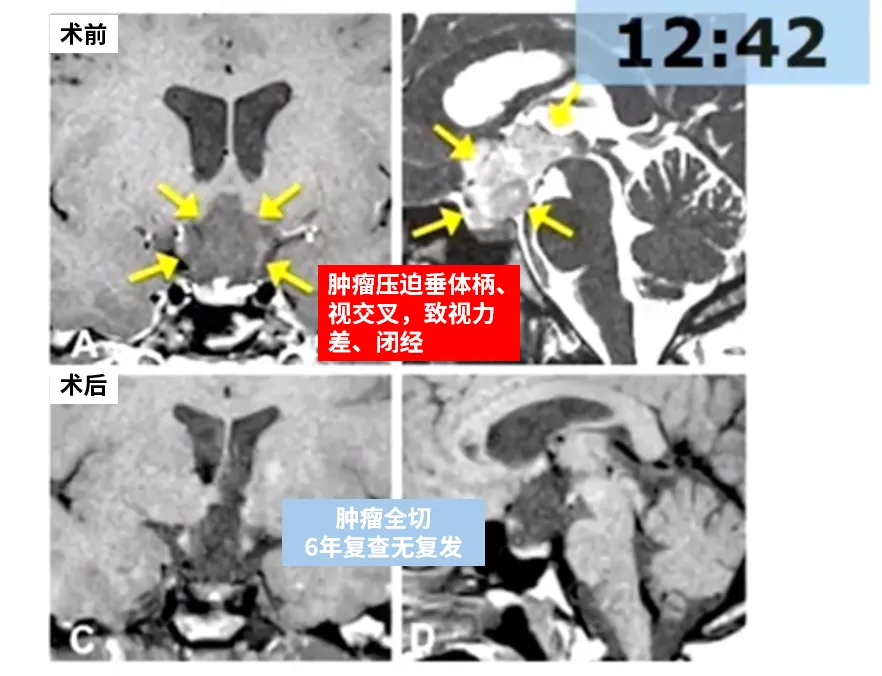

医院检查结果显示,我的颅内长有一个巨大视路-下丘脑肿瘤(如黄色箭头所示),肿瘤已向第三脑室深部延伸(图A、B)。由INC巴特朗菲教授主刀实施开颅手术后,术后MRI证实肿瘤达到全切(图C、D)。术后病理报告确认为毛细胞星形细胞瘤。经过6年随访观察,我恢复状况良好,未出现任何症状且无肿瘤复发迹象,下丘脑-垂体功能保持完整。我深感幸运,因为这属于良性肿瘤范畴!